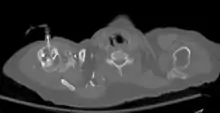

The needle is inserted through the bone's hard cortex and into the soft marrow interior, which allows immediate access to the vascular system. The IO needle is positioned at a 90 degree angle to the injection site, and is advanced through manual traction, impact driven force, or is power driven. Each IO device has different designated insertion locations. The most common site of insertion is the antero-medial aspect of the upper, proximal tibia as this site lies just under the skin and is easily located. Other insertion sites include the anterior aspect of the femur, the superior iliac crest, proximal humerus, proximal tibia, distal tibia and the sternum (manubrium).[1] Although intravascular access is still the preferred method for medication delivery in the prehospital area, IO access for adults has become more common. As of 2010, American Heart Association no longer recommends using the endotracheal tube (ET )for resuscitation drugs, except as a last resort when IV or IO access cannot be gained.[1] ET absorption of medications is poor, and optimal ET drug dosings are unknown. IO administration is becoming more common in civilian and military pre-hospital emergency medical services (EMS) systems globally.[11]